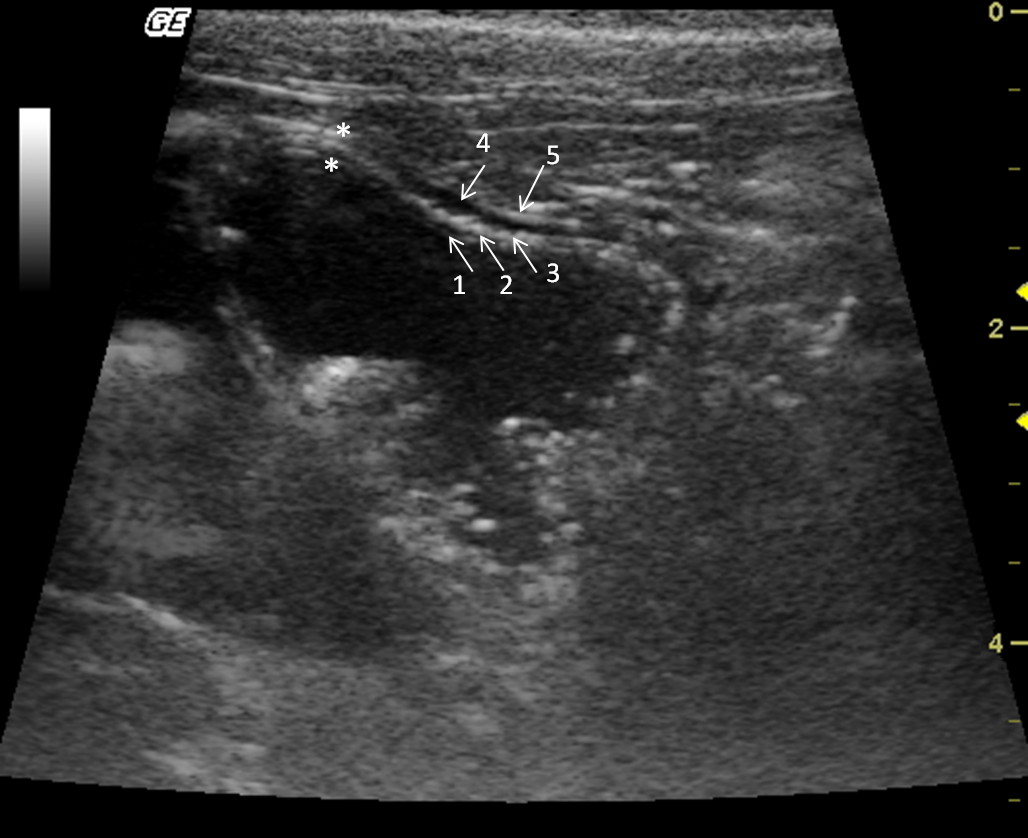

The stomach was observed caudal to the liver. Mild peristaltic activity was present, but it could not be quantitatively assessed because the animals were under anaesthesia. The stomach was distended by gas, and in spite of fasting, there was mild to moderate amount of anechoic content with hyperechogenic sediments, indicating the presence of water and food remnants. The average wall thickness was 2.8 mm. There were four layers alternating between hyperechogenic and hypoechogenic (Fig. 6). Stomach wall layering was detected in all individuals, the gastric mucosa and muscularis layers were anechoic, whereas the sub-mucosa and serosa were hyperechoic. During post-mortem examination the gastrointestinal tract structures were identified (Fig. 7).

Figure 6.

Transverse sonogram of the Alouatta fusca stomach. This structure is filled with anecoic (liquid) and hyperechogenic dots (food remains). The gastric wall has alternated echogenic pattern (arrows) (1) lumen; (2) mucosa; (3) submucosa; (4) muscularis; (5) serosa.